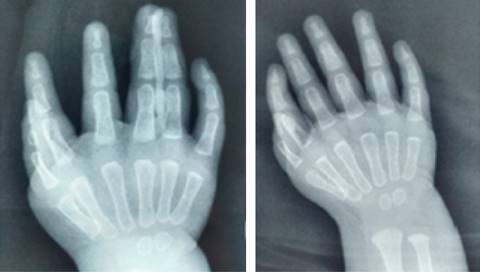

Physical examination presented (Figure 1) both symmetrical thoracic extremities, without shortening nor scapular waist or joint elbows deformities, with posterior hypoplastic forearm musculature, without limitation for prone-supination, both wrists in flexion pose at 40o, limited to 20° extension. The hands with the presence of 6 fingers in both hands in an attitude of flexion, presenting three post-axial triphalangeal fingers and three preaxial, morphologically normal. The examination shows complete mobility arches in shoulders and elbows, without joint instability, with limitation in both wrists (palmar flexion of 75°, dorsal extension 20°, abduction and adduction 5°), the arcs of mobility of the postaxial fingers was normal, and the preaxial fingers showed complete mobility arcs but decreased strength 4/5 on the Daniel’s scale, without pain. Simple X-rays of both hands were requested (Figure 2), finally integrating the diagnosis of bilateral mirror hand syndrome.

Figure 2: Simple hand X-ray: polydactyly is observed, with the presence of 6 metacarpal bones with their respective phalanges, with absence of thumb, presence of 2 nuclei of ossification of the carpus and radio-ulnar growth physis. Six triphalangic fingers are seen in both hands, with a distal hypoplastic phalanx of the first radial finger of the left hand.